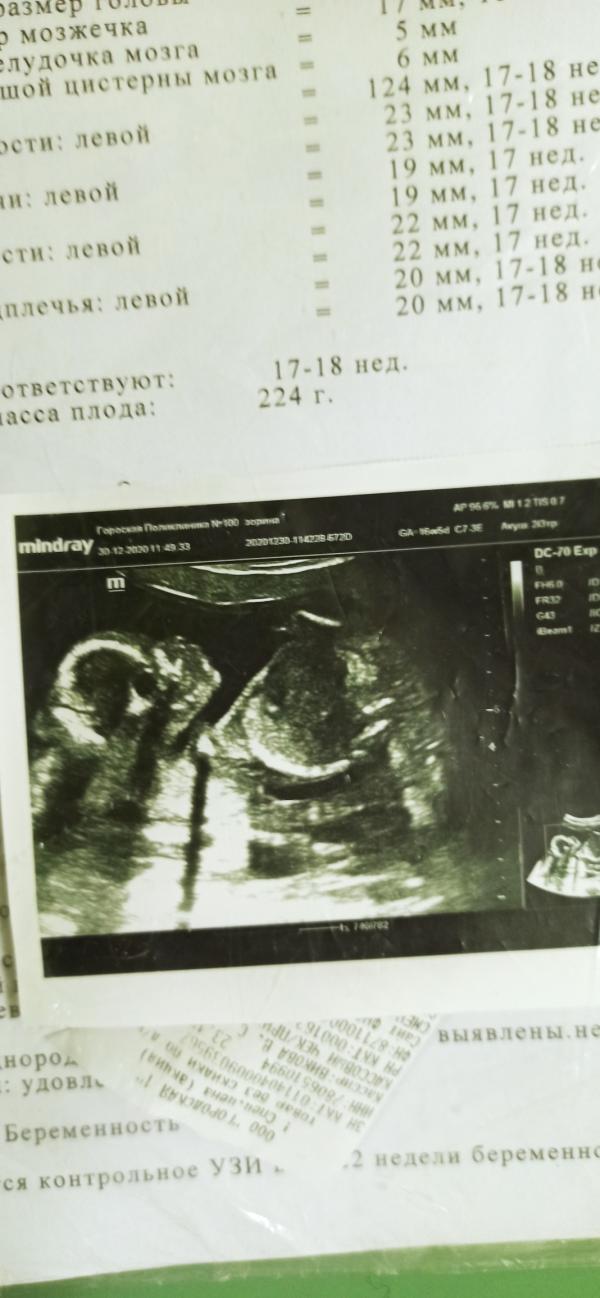

Вчера (29.12.2020) была на УЗИ!!! У нас будет мальчик! Сын!!! Подарок мужу! Теперь у нас и дочка и сын будут!!! Как и мечтали!

По развитию опережает срок на неделю!